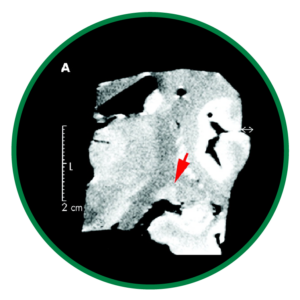

La neurodegeneración glaucomatosa se extiende más allá del nervio óptico, afectando estructuras cerebrales clave como el núcleo geniculado lateral y la corteza visual. Estudios de neuroimagen han demostrado atrofia y alteraciones funcionales en estas áreas, lo que confirma que el glaucoma implica un compromiso del procesamiento visual central.2

La resonancia magnética muestra cambios estructurales y reducción del tamaño del núcleo geniculado lateral en el glaucoma frente a controles.2